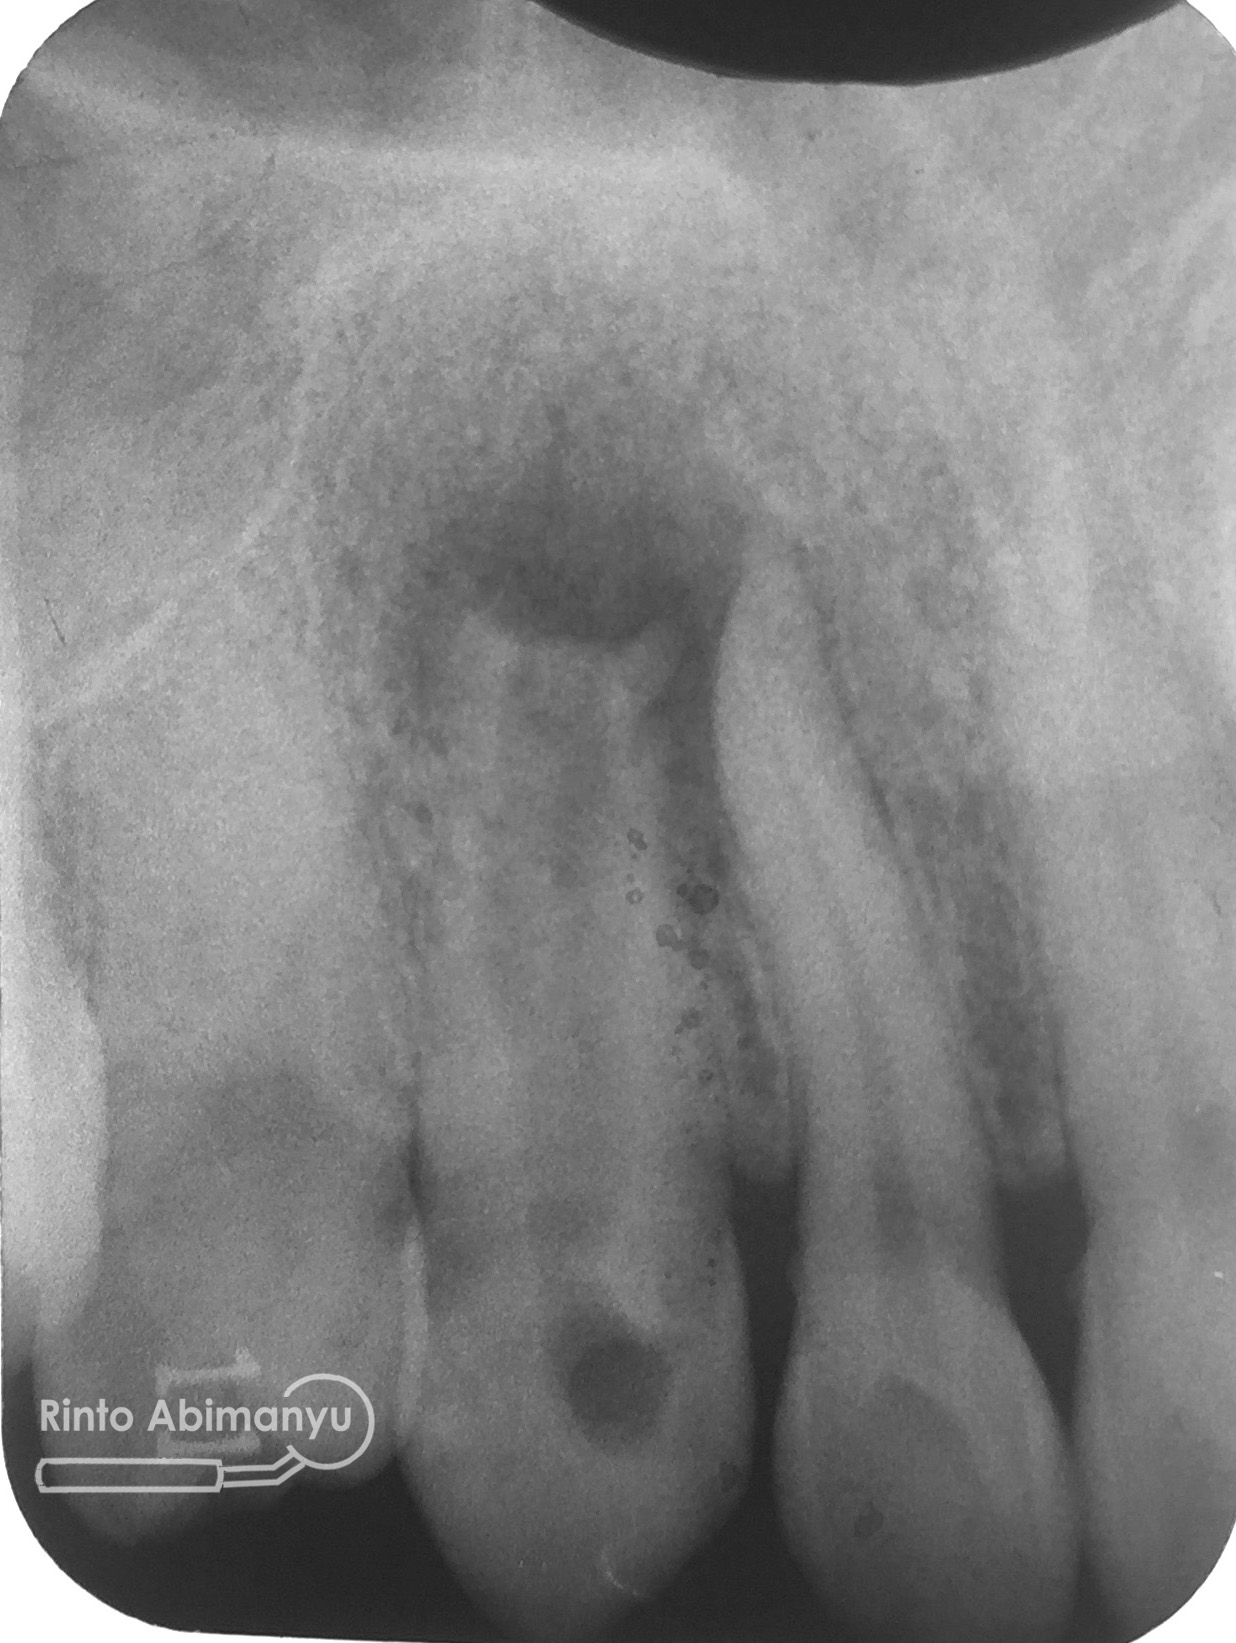

Setelah akses ke kamar pulpa didapat, lalur dirapihkan agar arah masuk file dapat lurus, maka selanjutnya adalah proses cleaning and shaping… Panjang kerja diukur menggunakan apex locator Root ZX mini (Morita) dan preparasi saluran akar menggunakan i3 Gold (Denjoy)… Irigasi memakai larutan NaOCl 5,25% dan diaktivasi menggunakan waterpik dan tip endoactivator…

Setelah proses cleaning and shaping dilakukan trial gutta percha untuk melihat apakah kon utama yang akan kita gunakan pas dengan saluran akarnya…

Setelah melihat hasil ronsen trial guttap maka pengisian siap dilakukan… Untuk pengisian saluran akar saya memakai tehnik warm vertival condensation memakai alat Element Obturation Unit (SybronEndo) dan siler AH plus (Dentsply)…